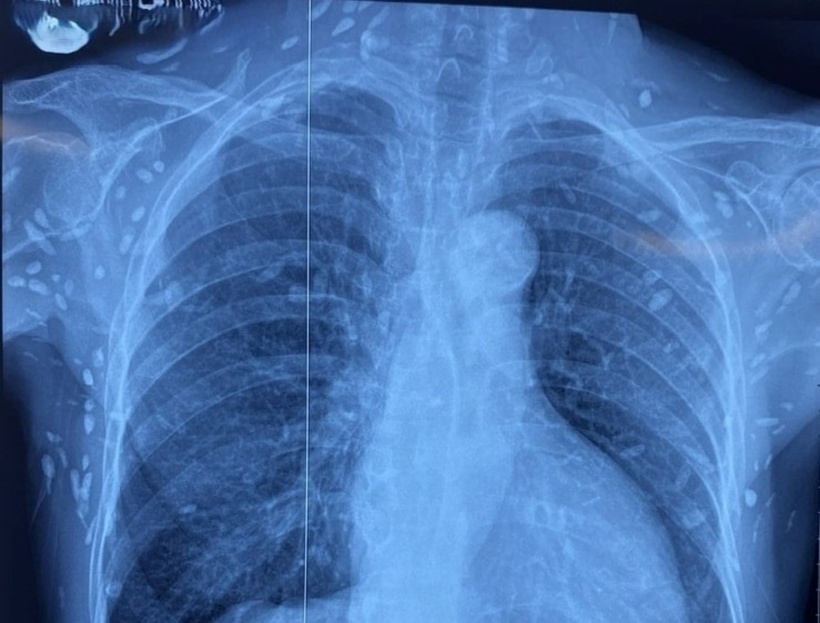

Bệnh nhân được chuyển lên từ tuyến trước trong tình trạng rối loạn ý thức, đe dọa suy hô hấp. Kết quả chụp CT sọ não và X-quang ngực cho thấy nhiều nốt cản quang trong nhu mô não và dưới da vùng ngực - bụng, gợi ý tổn thương do sán dây lợn.

Nhiều nốt cản quang dưới da thành ngực - bụng và chi trên của bệnh nhân. Ảnh: Tạp chí Tri Thức.

Theo ThS.BS Nguyễn Sỹ Thấu, khoa Hồi sức Truyền nhiễm, một số u cục nhỏ có thể sờ thấy dưới da vùng ngực và cánh tay của bệnh nhân. Dù xét nghiệm kháng thể IgM với sán dây lợn âm tính, hình ảnh X-quang cho thấy bệnh nhân đã từng nhiễm ấu trùng sán dây lợn, sau đó các nang sán thoái hóa, vôi hóa và tồn tại lâu dài trong mô.